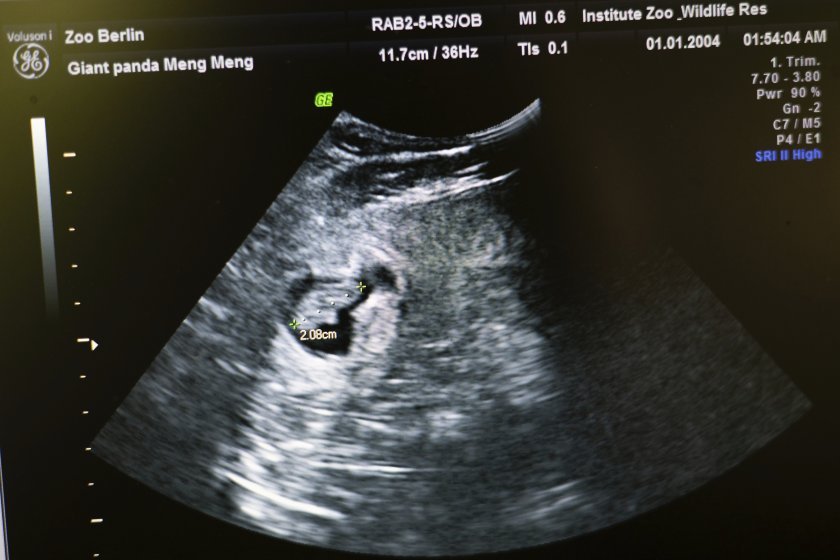

Малките пристигнаха на бял свят в четвъртък и се усещат добре, оповестяват от зоопарка. Те са родени единствено 11 дни, откакто ултразвуковите проучвания демонстрираха, че 11-годишната Мън Мън е бременна. Полът на новородените към момента не е избран „ сигурно “.